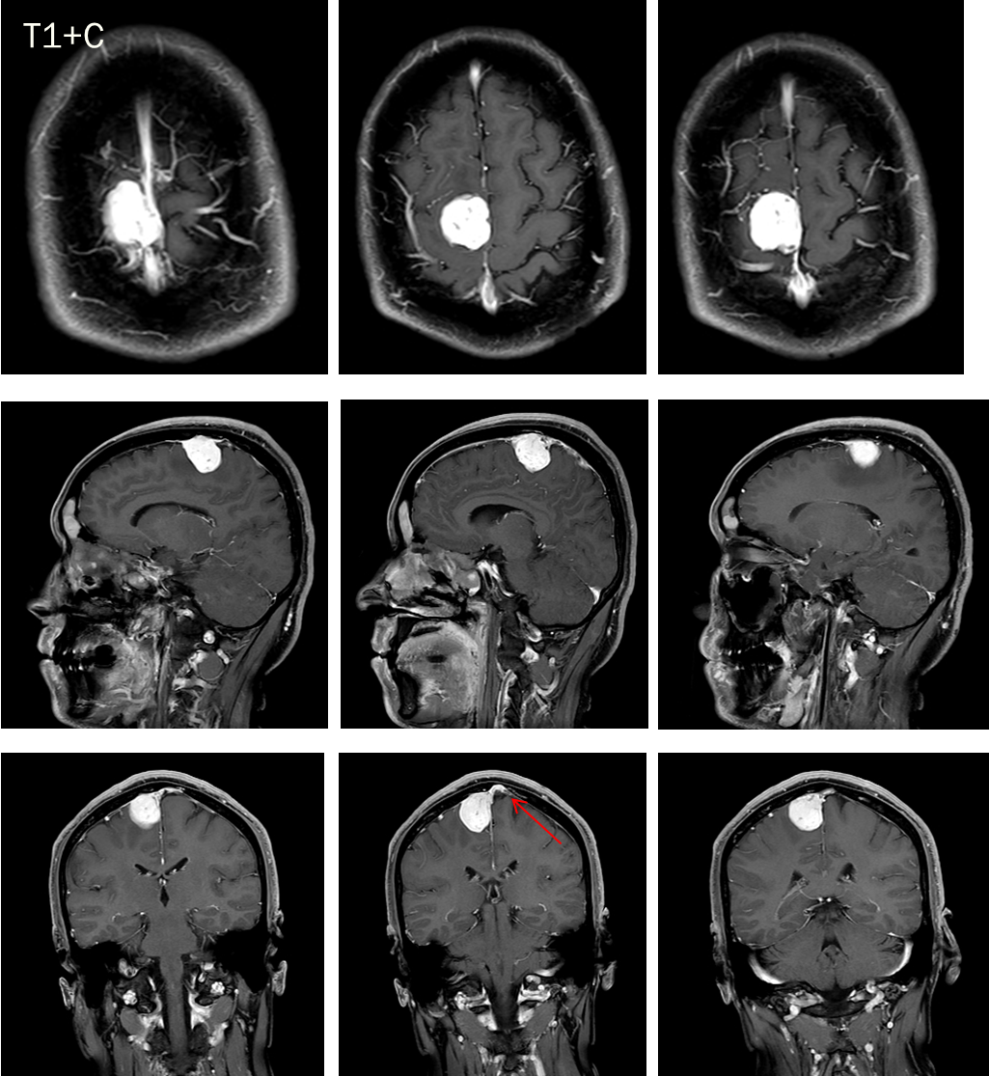

CASE 2

男,34 岁

右侧顶部大脑镰旁占位,信号均匀,增强可见明显强化,边界清晰,见脑膜尾征。

诊断:右侧顶部脑膜瘤